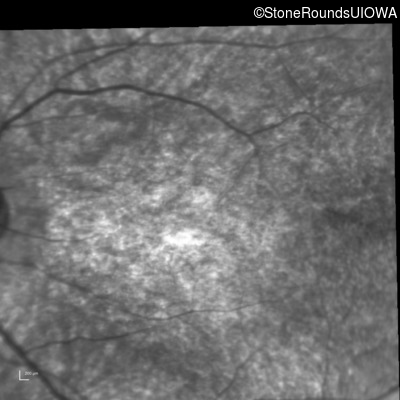

Infrared Fundus Photograph - Left - 10/160 -1

Exemplar